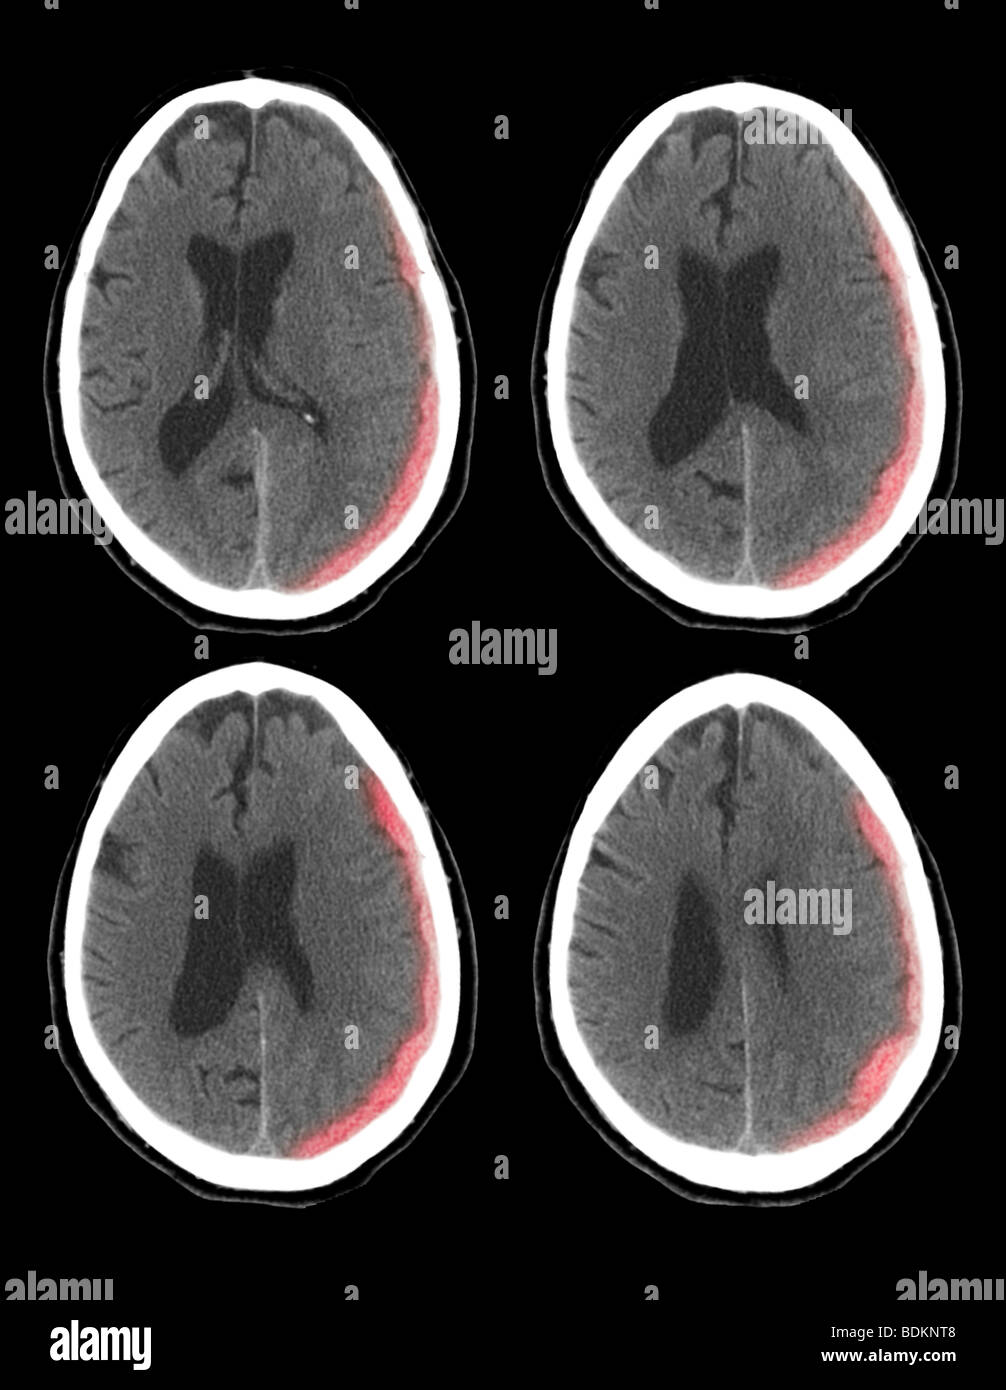

Scanographie du cerveau d'un homme de 73 ans montrent une hémorragie intracrânienne Banque D'Imageshttps://www.alamyimages.fr/image-license-details/?v=1https://www.alamyimages.fr/photo-image-scanographie-du-cerveau-d-un-homme-de-73-ans-montrent-une-hemorragie-intracranienne-25635128.html

Scanographie du cerveau d'un homme de 73 ans montrent une hémorragie intracrânienne Banque D'Imageshttps://www.alamyimages.fr/image-license-details/?v=1https://www.alamyimages.fr/photo-image-scanographie-du-cerveau-d-un-homme-de-73-ans-montrent-une-hemorragie-intracranienne-25635128.htmlRMBDKNT8–Scanographie du cerveau d'un homme de 73 ans montrent une hémorragie intracrânienne